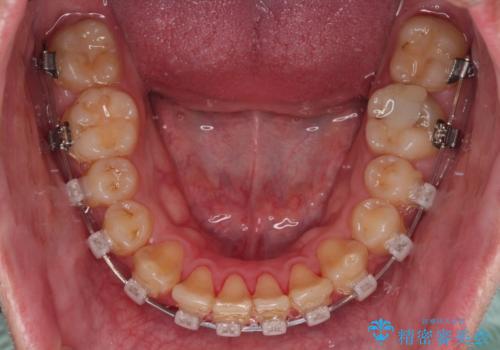

- クリアブラケット

補助装置を用いて上顎歯列全体を後方に移動させる力をかけ、唇が閉じやすいような仕上がりを目指して、ワイヤー装置にて矯正治療を行うこととしました。

非常に咬合力が強く、左側の臼歯がなかなか後方へ移動できなかったのですが、2年ほどかけて大変満足のいく仕上がりを達成することができました。